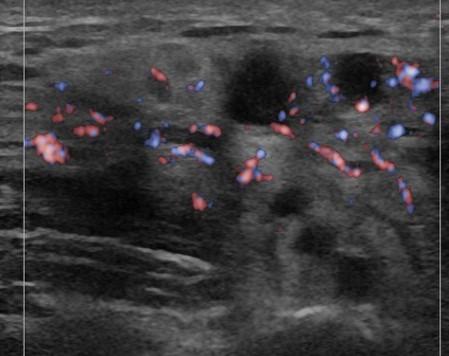

Viêm tuyến nước bọt

» Thông tin: Nam giới – 16 tuổi.

» Lâm sàng: Sưng đau vùng góc hàm từng đợt.

# Viêm tuyến nước bọt dưới hàm mạn tính.